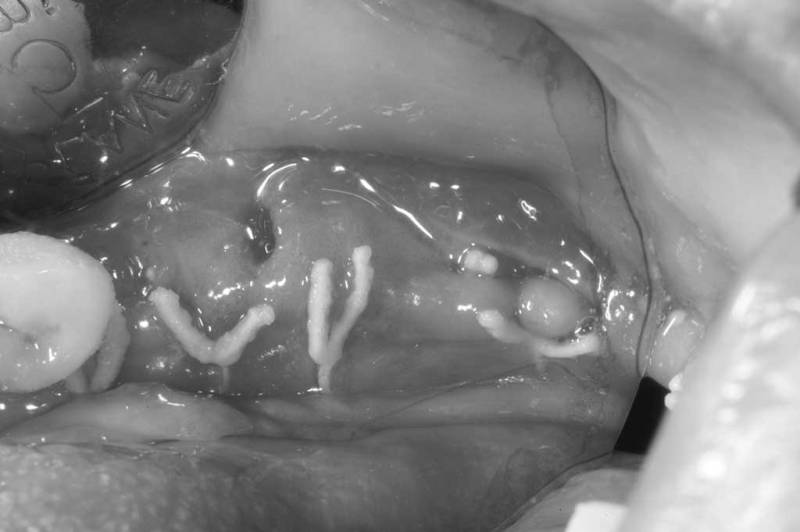

骨脊增厚術術中